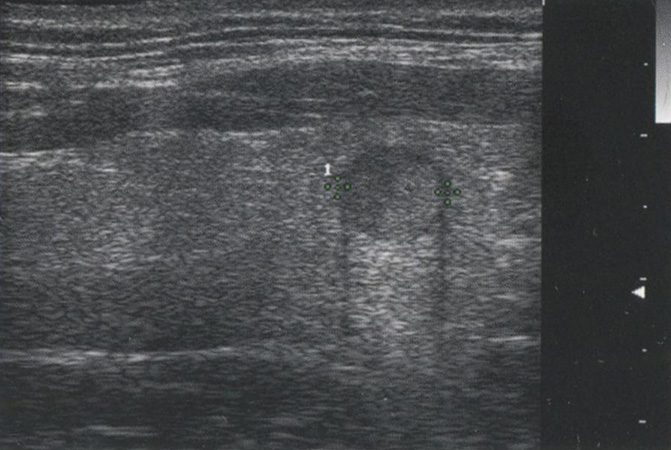

На рис. 2.15 изображен узел с кальцификацией по типу «яичной скорлупы». Слой кальция, окружающий узел, приводит к отсутствию сигнала позади узла. Видно, что наибольшее отражение возникает от поверхностей, расположенных перпендикулярно звуковым волнам. Поскольку угол падения приближается к 180° вдоль боковых стенок, большинство отраженных волн не возвращается на датчик, уменьшая интенсивность сигнала, отвечающего за боковые части структуры.

Рис. 2.15. Кальцификация по типу «яичной скорлупы». Слой кальция, окружающий узел, приводит к отражению от поверхности с выраженной акустической тенью по всей линии